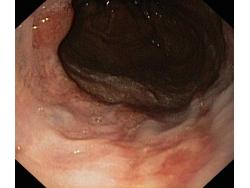

Obrazy endoskopowe

Choroba refluksowa